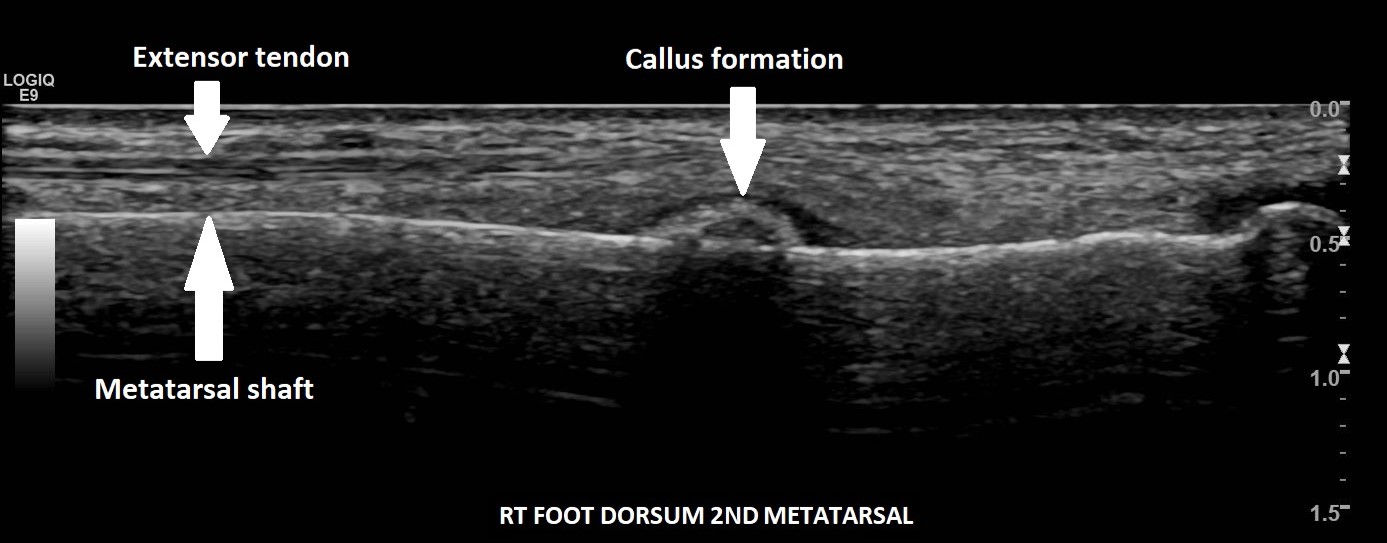

A 29-year-old female, presented with pain and a lump on the dorsum of her right foot. She was training for a 10km run and had been struggling with running over a 6-week period. No history of trauma or erythema to the skin. The clinical suspicion was a ganglion, and the patient was referred for an ultrasound scan for further assessment.

On the dorsum of the foot, ultrasound demonstrated marked cortical irregularity and callus formation around the third metatarsal shaft accounting for the palpable ‘lump’ with surrounding soft tissue swelling (Figure 1). On power Doppler, there was marked peripheral vascularity in the surrounding soft tissues (Figure 2). Incidentally, there was also cortical irregularity and callus formation around the second metatarsal shaft although the patient was not particularly tender here whilst scanning (Figure 3). The cortical irregularity in the second metatarsal shaft was minimal when compared to the third metatarsal and there was no neovascularisation on power Doppler indicating this was an older/mature injury.

Ultrasound appearances in keeping with acute and chronic stress fractures. A radiograph confirmed old and new callus formation (Figure 4). Conservative treatment comprised rest and analgesia. Surgery is generally reserved for stress fractures that do not heal.